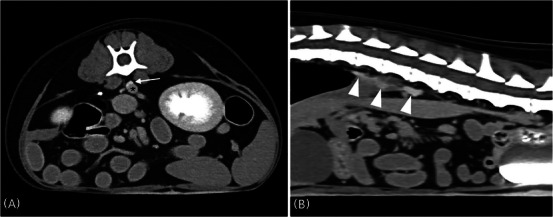

The intestinal vicarious contrast medium excretion (VCME) can occur in dogs with protein-losing enteropathy (PLE), and studies for intestinal VCME in dogs are lacking. This retrospective case-control study aimed to assess whether intestinal VCME could be observed on delayed CT in dogs with and without PLE. Thirty dogs who underwent abdominal delayed CT in the 10 min-delayed phase following the injection of contrast medium were enrolled. Six dogs were classified into the group with enteropathy based on imaging findings or abnormal results from cytology or histology. The six dogs had concurrent hypoalbuminemia and were diagnosed with presumed PLE. Five of the six dogs in the group with enteropathy had intestinal VCME. In the 24 dogs of the group without enteropathy, intestinal VCME was not detected on delayed CT, and VCME to the cisterna chyli was observed in one dog. The frequency of intestinal VCME was significantly higher in the group with enteropathy than in the group without enteropathy (p < .001). The presence of intestinal VCME on the delayed CT can be observed in dogs with PLE, and it can be used as noninvasive additional supportive evidence of canine PLE prior to histopathologic evaluation.

Abstract Image